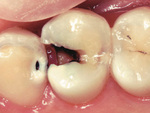

虫歯を放置すると、エナメル質の損傷が深刻化し、歯の内部の象牙質にまで進行します。この段階では、虫歯が見た目に黒くなったり、食べ物がしみる痛みが出てきます。また、進行が進むと歯の神経まで感染が広がり、激しい痛みを伴うことがあります。

歯の表面に白い斑点や黒い点が現れた場合、虫歯が進行しているサインです。進行具合の確認は歯科医師にお願いするのが確実です。